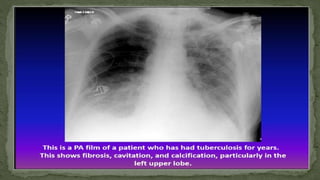

D. Tuberculosis

Chest x ray interpretation